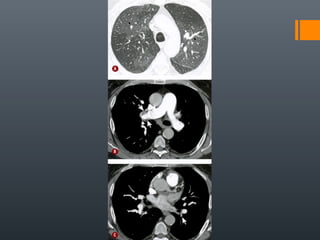

O documento discute vários conceitos radiológicos incluindo consolidação, atelectasia, nódulos, pseudocavidades e padrões intersticiais, fornecendo definições, sinais e diagnósticos diferenciais para cada tópico. Ele também discute a redução da atenuação pulmonar e fornece um link para mais informações.